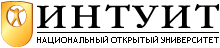

Из разных типов таких аппаратов, которые промышленно выпускаются, а их десятки, ознакомим Вас лишь с несколькими портативными. На рис. 7.5 слева показан современный аппарат SonoAce Pico для УЗ сканирования человеческого тела. Будучи переносным (357x320x204 мм, масса меньше 10 кг), он имеет практически такие же диагностические возможности, как и традиционные стационарные аппараты для УЗИ. Благодаря цифровой технологии формирования УЗ пучков и обработки сигналов он позволяет получать цветные изображения состояния внутренних органов с высокой разрешающей способностью.

Кроме возможности формирования объемных изображений и применения широкополосных мультичастотных датчиков, он может выполнять функции формирования трапецеидального изображения, увеличения масштаба изображения при исследовании малых органов. Он рассчитан также на применение микроконвексного датчика, имеет программы кардиологических исследований. Возможная глубина сканирования – до 30 см. В базовую комплектацию входят также электрокардиографический модуль с программным обеспечением, система SonoView  Lite для архивации и дальнейшего просмотра эхограмм, ёмкая память, выходы для одновременного присоединения к базовому блоку двух датчиков.

Lite для архивации и дальнейшего просмотра эхограмм, ёмкая память, выходы для одновременного присоединения к базовому блоку двух датчиков.

Возможно применение многих прогрессивных технологий ультрасонографии:

Multi-beam – технология цифрового формирования УЗ пучков с подавлением влияния многократных отражений, нелинейных искажений, неточности интервалов задержки и т.п.

OTI  (Optimum Tissue Imaging) – технология формирования оптимального изображения ткани благодаря коррекции скорости (выбор оптимальной скорости для каждой области, чтобы обеспечить высокое качество изображений одновременно всех видов ткани, таких как жировая, мышцы или паренхима печени).

(Optimum Tissue Imaging) – технология формирования оптимального изображения ткани благодаря коррекции скорости (выбор оптимальной скорости для каждой области, чтобы обеспечить высокое качество изображений одновременно всех видов ткани, таких как жировая, мышцы или паренхима печени).

THI  (Tissue Harmonic Imaging – "тканевая" или вторая гармоника) – повышает качество изображений, их контраст и линейную разрешающую способность у пациентов с затрудненной визуализацией (например, с толстыми жировыми прослойками).

(Tissue Harmonic Imaging – "тканевая" или вторая гармоника) – повышает качество изображений, их контраст и линейную разрешающую способность у пациентов с затрудненной визуализацией (например, с толстыми жировыми прослойками).

OHI  (Optimized Harmonic Imaging) – применяется в особо трудных для исследования случаях.

(Optimized Harmonic Imaging) – применяется в особо трудных для исследования случаях.

FINE  (Filtered Image for Noise reduction & Edge enhancement) – технология улучшенной фильтрации УЗ сигналов, которая уменьшает уровень шумов и обеспечивает более высокий контраст.

(Filtered Image for Noise reduction & Edge enhancement) – технология улучшенной фильтрации УЗ сигналов, которая уменьшает уровень шумов и обеспечивает более высокий контраст.

CAFE  (Compound Automatic Flash Elemination) – обеспечивает адаптивную нелинейную фильтрацию для удаления цветных точек, которые возникают вследствие случайных артефактов. Улучшает визуализацию кровотока в доплеровских режимах.

(Compound Automatic Flash Elemination) – обеспечивает адаптивную нелинейную фильтрацию для удаления цветных точек, которые возникают вследствие случайных артефактов. Улучшает визуализацию кровотока в доплеровских режимах.

Ультразвуковой диагностический сканер Fukuda UF-750XT показан справа на рис. 7.5. Он предназначен для неотложной (на выездах) УЗ функциональной диагностики сердечно-сосудистых заболеваний, щитовидной и молочной желез, почек, печени, желудка, желчного пузыря, половых органов. Цветной жидкокристаллический дисплей с диагональю 265 мм обеспечивает высокое качество изображений. Общие габаритные размеры сканера 380x220x370 мм, масса – меньше 13 кг. Оснащен магнитооптическим диском памяти на 640 Мбайт, на котором могут храниться до 6 тысяч эхограмм. Имея приблизительно такие же функциональные возможности, как и предыдущий сканер, он обеспечивает также УЗ исследование слабого и медленного кровотока.

Еще меньшие размеры и массу (78x350x280 мм и 4,5 кг) имеет созданный фирмой General Electric Medical Sуstems УЗ сканер Logiq Book, ( рис. 7.6). Он тоже цифровой, используется собственная информационная технология TruScan фирмы GE, обеспечивающая высокое качество изображений, лучшие возможности обработки данных и высокий уровень эргономичности.

В состав программного обеспечения входят:

- программные пакеты для измерений, вычислений и автоматического создания отчетов (для акушерства, кардиологии, ангиологии, радиологии, урологии, гинекологии, хирургии, педиатрии);

- программы объемной реконструкции с возможностью мультипланового анализа, поддержки протокола беспроводной связи;

- программа формирования и поддержки базы данных пациентов с возможностью переноса данных на внешние носители и на внешний компьютер.